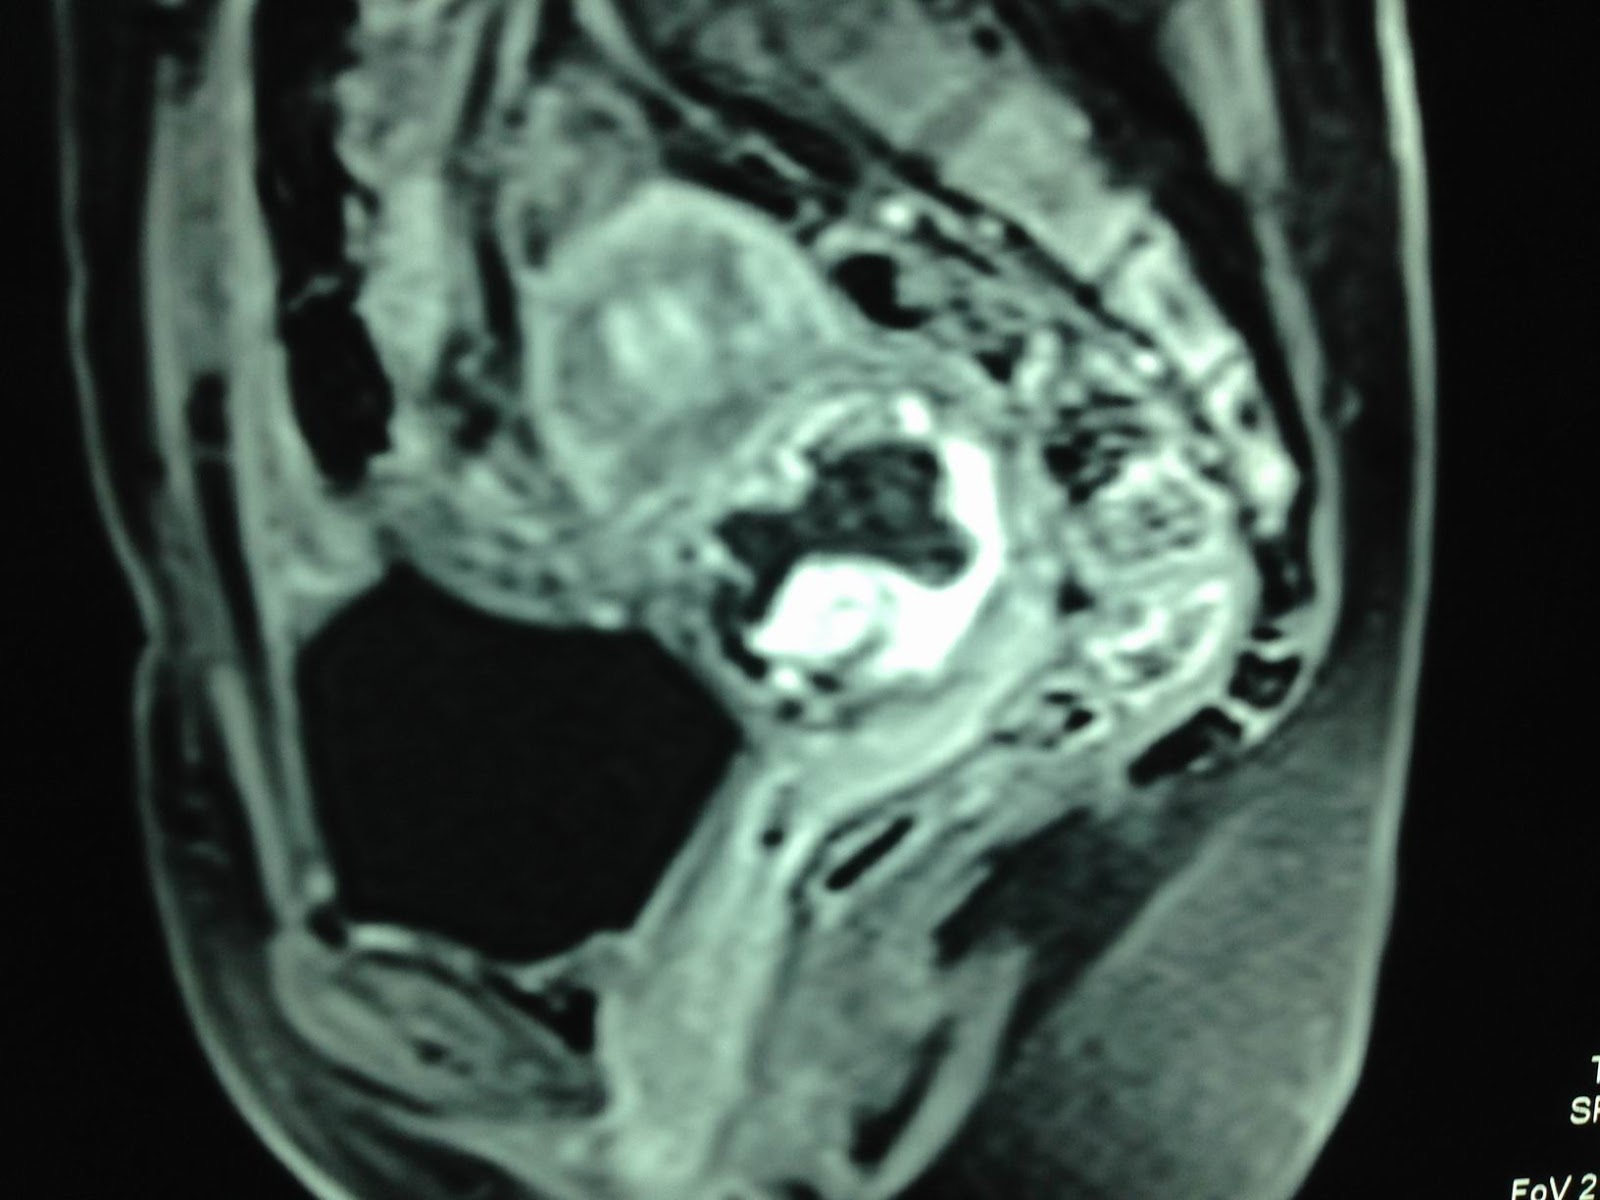

MRI uterusof this mass suspected gestation at neck uterus in the scar of cesarian section before.

Open operation for hysterectomy confirmed cervical pregnancy in C-section scar.